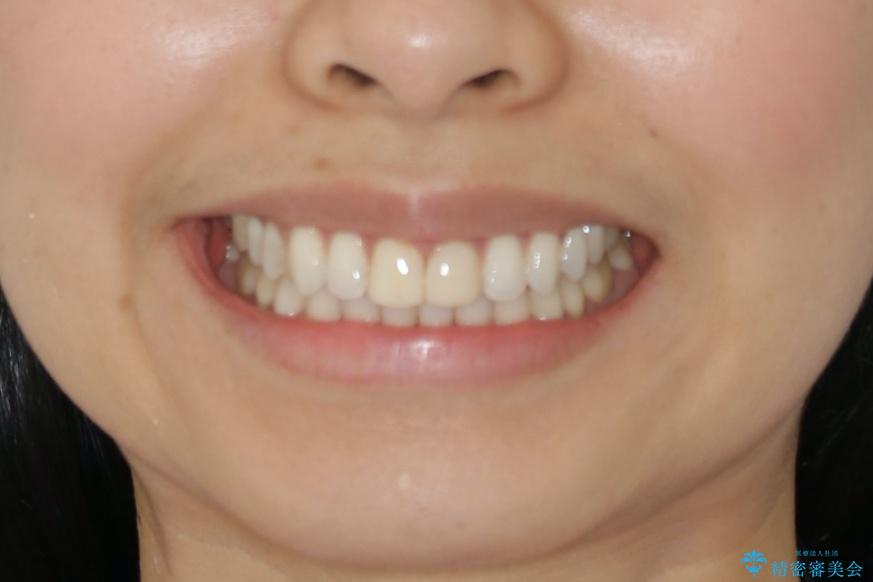

すきっ歯を治したい。インビザライン・ライトによる矯正治療

- 正中離開を気にされて来院された患者様です。

インビザラインでの治療を希望され、正中離開のみ治したいとのことだったので、インビザライン・ライト(片顎)での治療を選択しました。

インビザライン・ライトは枚数が少ないため歯の移動量に限界がありますが、短期間での治療が可能です。